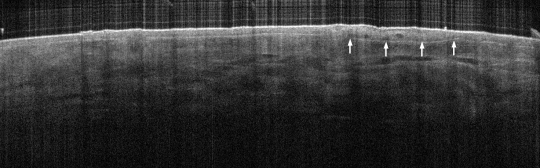

VA35: Left Temple, Actinic Keratosis, Hypertrophic

- White arrows indicate return to dermal collagen texture and reflectivity

VA35: Left Temple, Adjacent, Normal